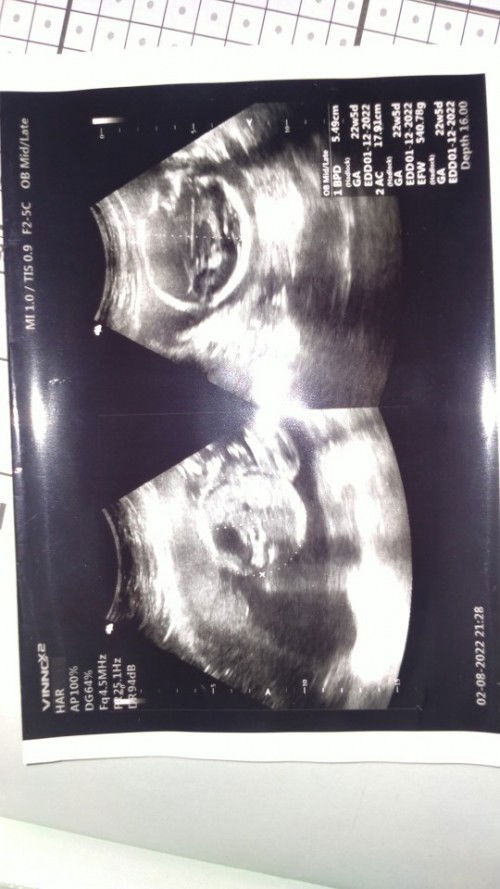

Bunda², aku udah lewat HPL 2 hari nih (HPL 23 Nov) Dan bidan ku WA minta foto hasil USG terakhir. Nah, di USG terakhir ini tgl 2 Agustus atau UK sekitar 22 minggu. Bidannya suruh lihat HPL hasil USG nya, disitu tertera 1 Desember bunda² Apa harus percaya hasil USG tsb atau yakin kalo posisi kita udah lewat HPL ? Khawatir bun karna udah lewat HPL yg dihitung bidan, tp rada seneng karna lihat hasil USG tsb.. Kek afirmasi positif kalo dedeknya belum waktunya aja keluar.. Jadi pendapat bunda² gimana aku baiknya? Maklum nge-blank otaknya mikir bun pas ditimpa situasi gini.. 😥#bantusharing #ingintahu #firstmom